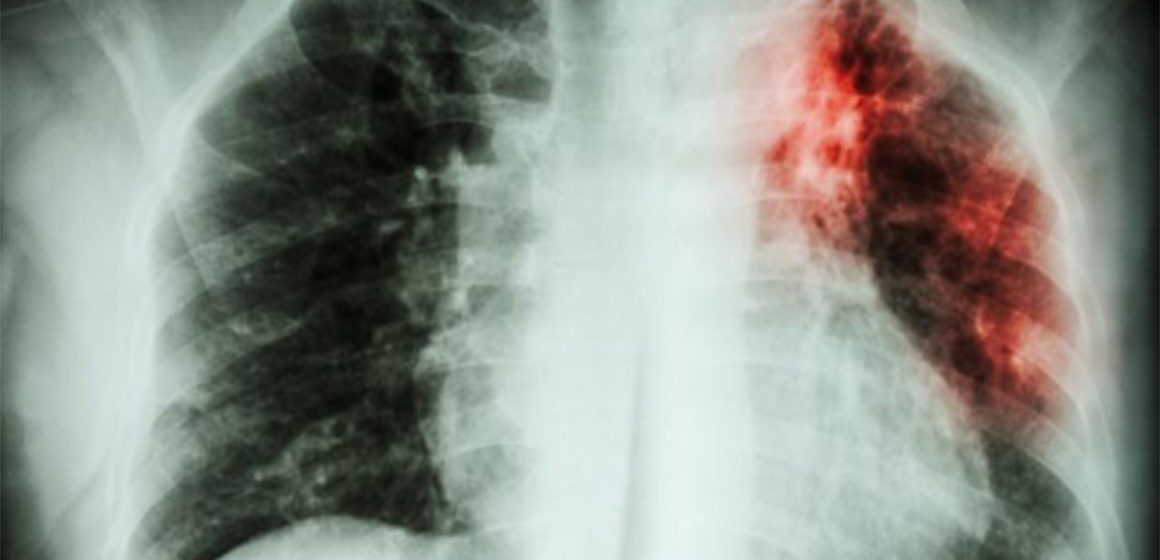

Plus de 11 800 cas de tuberculose, dont 336 décès, ont été recensés en 2023 dans la province de l’Ituri. Cette maladie continue de se propager dans la région en raison de l’accès difficile aux soins, notamment à cause de la destruction ou de l’incendie de nombreuses structures sanitaires par les groupes armés.

Ces informations ont été révélées mercredi 10 juillet par le Programme Lèpre et Tuberculose lors d’une matinée scientifique organisée à l’Université Shalom de Bunia. Selon le Dr Justin Mukonkole, coordonnateur du programme, la difficulté d’accès aux structures sanitaires, dont la plupart ont été incendiées ou détruites par les milices, est la principale cause de la propagation de la tuberculose en Ituri.

Une forte prévalence de la maladie est observée dans les zones minières, qui représentent environ 50% des patients. Les zones de santé les plus touchées sont Bambu, Nizi, Mangala, Mongbwalu (territoire de Djugu), Bunia et Rwampara (territoire d’Irumu), et Nia Nia (territoire de Mambasa). Parmi les patients tuberculeux en Ituri, on compte environ 1 200 enfants. Le nombre de cas en augmentation constante

Le Dr Mukonkole souligne que le nombre de malades ne cesse de croître à cause des difficultés d’accès aux soins. En effet, plusieurs structures sanitaires dédiées à la prise en charge de la tuberculose ont été détruites ou incendiées par les milices. D’autres ne sont pas opérationnelles en raison de l’insécurité persistante.